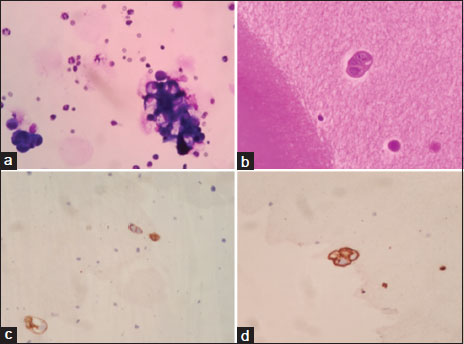

On evaluation, magnetic resonance imaging brain and thoraco-lumbo-sacral spine showed heterogeneous hyperintense lesion [Figure 1] in the parasagittal region and patchy dural enhancement in the cervicodorsal region. Videostroboscopy showed left vocal cord palsy. Fluorodeoxyglucose PET-CT ruled out disease at other sites. These findings pointed to bulbar palsy as a possible cause of his hoarseness of voice and dysphagia. The bulbar palsy was likely a result of leptomeningeal disease. CSF was planned to confirm the same. CSF showed atypical cells, which were suspicious of malignancy, CSF protein was 266.7 mg/dl, and glucose was 29.4 mg/dl. To confirm the diagnosis and primary, IHC markers were done on cell blocks from CSF [Figure 2]. Cell block from CSF showed malignant cell clusters in [Figure 2]a and [Figure 2]b. CK7-positive cells are in [Figure 2]c and MUC-1 (Mucin-1, cell surface associated protein (clone MMAB,BioSB))-positive cells in [Figure 2]d. Cells were negative for CK20 and CDX2. Diagnosis of metastatic adenocarcinoma was confirmed on CSF with strong MUC1 staining favoring pancreatobiliary origin. For dysphagia, nasogastric feeding was started. Intrathecal chemotherapy (IT) was given with methotrexate and hydrocortisone weekly. Post 3 weeks of IT chemotherapy, the patient had symptomatically improved. However, the patient succumbed to chest infection in April 2020.

| Figure. 2 (a) Cytocentrifuge smears from cerebrospinal fluid showing few malignant cell clusters in hemorrhagic background (MGG stain, original magnification × 400). (b) Section from cell block reveals only an occasional malignant epithelial cell cluster (H and E stain, original magnification × 400). (c) Immunohistochemistry for CK7 shows positive staining in tumor cells (CK7 immunohistochemistry, original magnification × 400). (d) Immunohistochemistry for MUC1 showing positive staining in tumor cells (MUC1 immunohistochemistry, original magnification × 400)

CSF analysis by IHC, fluorescent in situ hybridization, polymerase chain reaction, and flow cytometry is known to improve the diagnostic rates. The sensitivity and specificity of IHC in LMC are 0.54 and 0.98, respectively.[7] IHC markers done on cell block from CSF in our case clearly established carcinomatosis (CK positive) and also confirmed hepatobiliary primary (MUC1, CK7 positive and CK 20, CDX2 negative).

| Figure. 2 (a) Cytocentrifuge smears from cerebrospinal fluid showing few malignant cell clusters in hemorrhagic background (MGG stain, original magnification × 400). (b) Section from cell block reveals only an occasional malignant epithelial cell cluster (H and E stain, original magnification × 400). (c) Immunohistochemistry for CK7 shows positive staining in tumor cells (CK7 immunohistochemistry, original magnification × 400). (d) Immunohistochemistry for MUC1 showing positive staining in tumor cells (MUC1 immunohistochemistry, original magnification × 400)